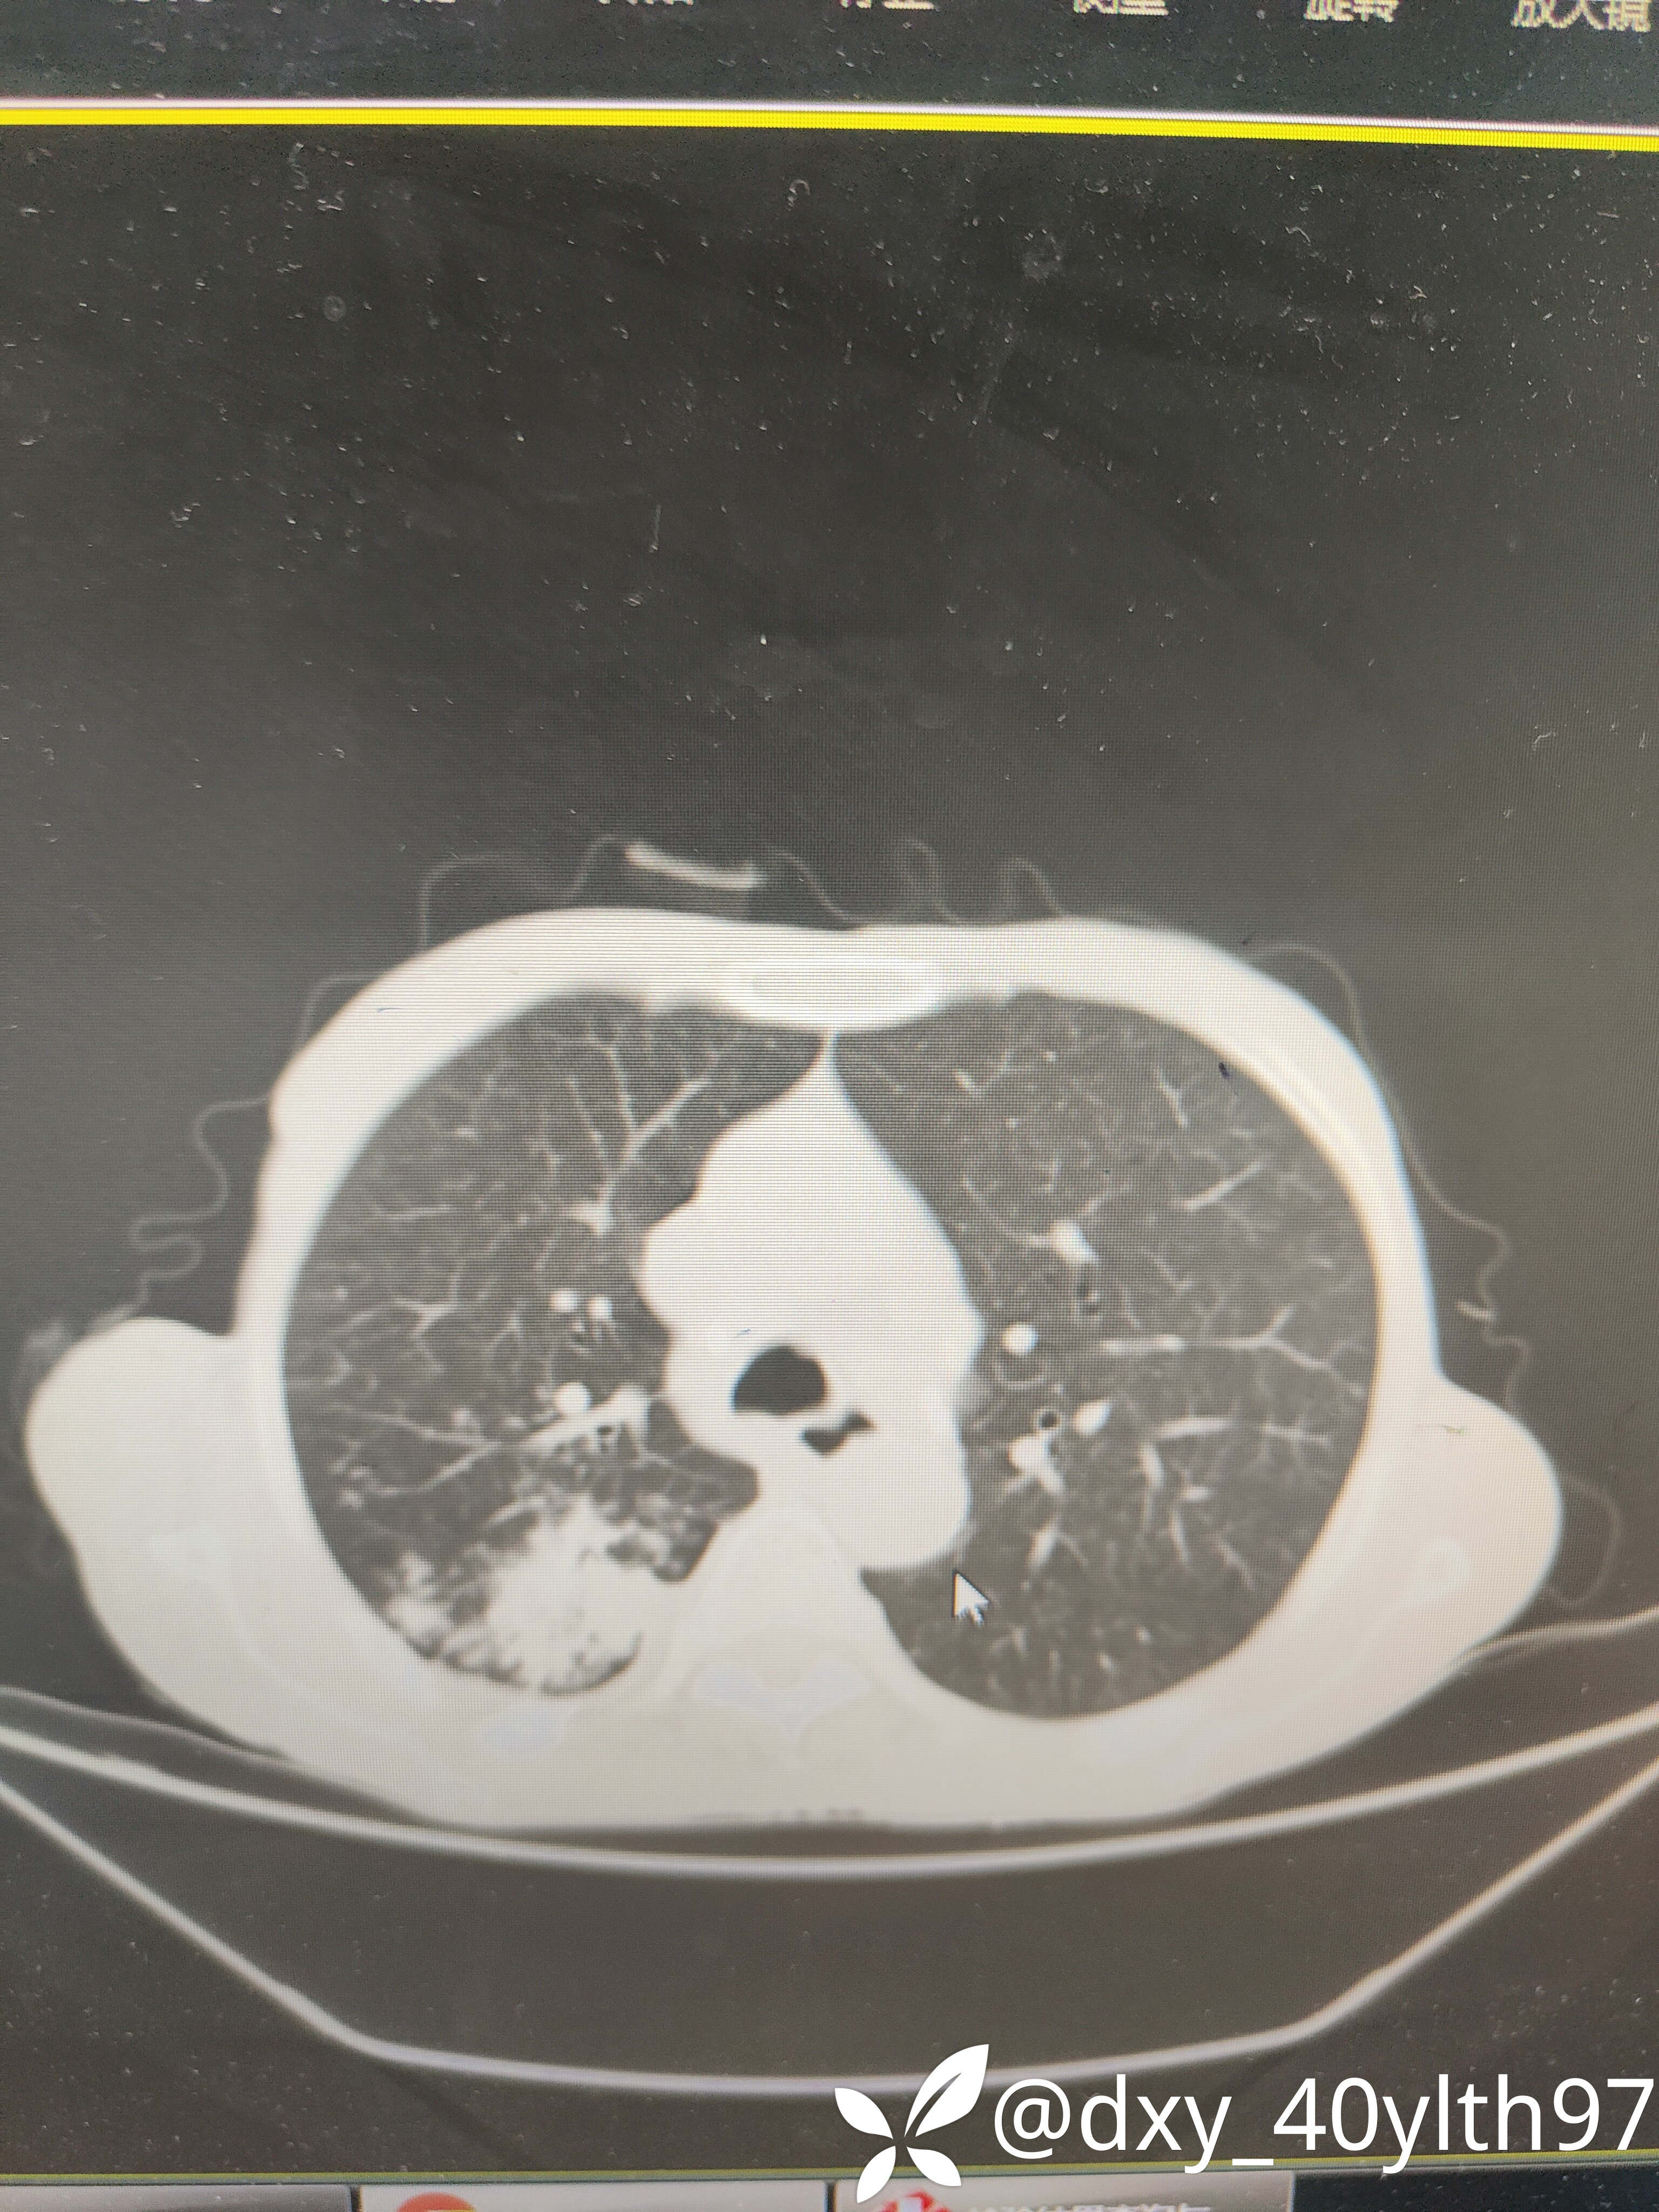

2023年8月肺部CT平扫影像结果提示:1.右肺上叶密度增高影较前显著增大,建议进一步检查;2.两肺多发斑片结节灶较前增多,部分增大。

肺部增强CT影像学提示:右肺内大片不规则影轻度强化,肿瘤可能。